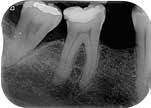

Fase diagnostica, che prevede una prima anamnesi clinica, una radiografia pre-operatoria per interpretare l’anatomia endodontica, al fine di definire un corretto piano di trattamento.

La diagnosi in endodonzia non può prescindere dall’esecuzione di esami radiologici accurati, in grado di mostrare l’esatta anatomia delle strutture dentali, in particolare dell’anatomia radicolare e dei tessuti di supporto.

Le apparecchiature radiologiche convenzionali (endorali) forniscono una rappresentazione bidimensionale di strutture anatomiche tridimensionali.

Questa immagine “appiattita” può nascondere, sovrapponendole, alcune aree anatomiche, soprattutto quelle in senso bucco-vestibolare (spessore dei tessuti).

Anche adottando tecniche radiografiche in grado di migliorare la qualità dell’immagine (tecnica del cono lungo con centratore “tipo Rinn”, proiezione dei raggi con inclinazione mesio-distale), i limiti tecnologici imposti dagli apparecchi endorali non sempre sono superabili.